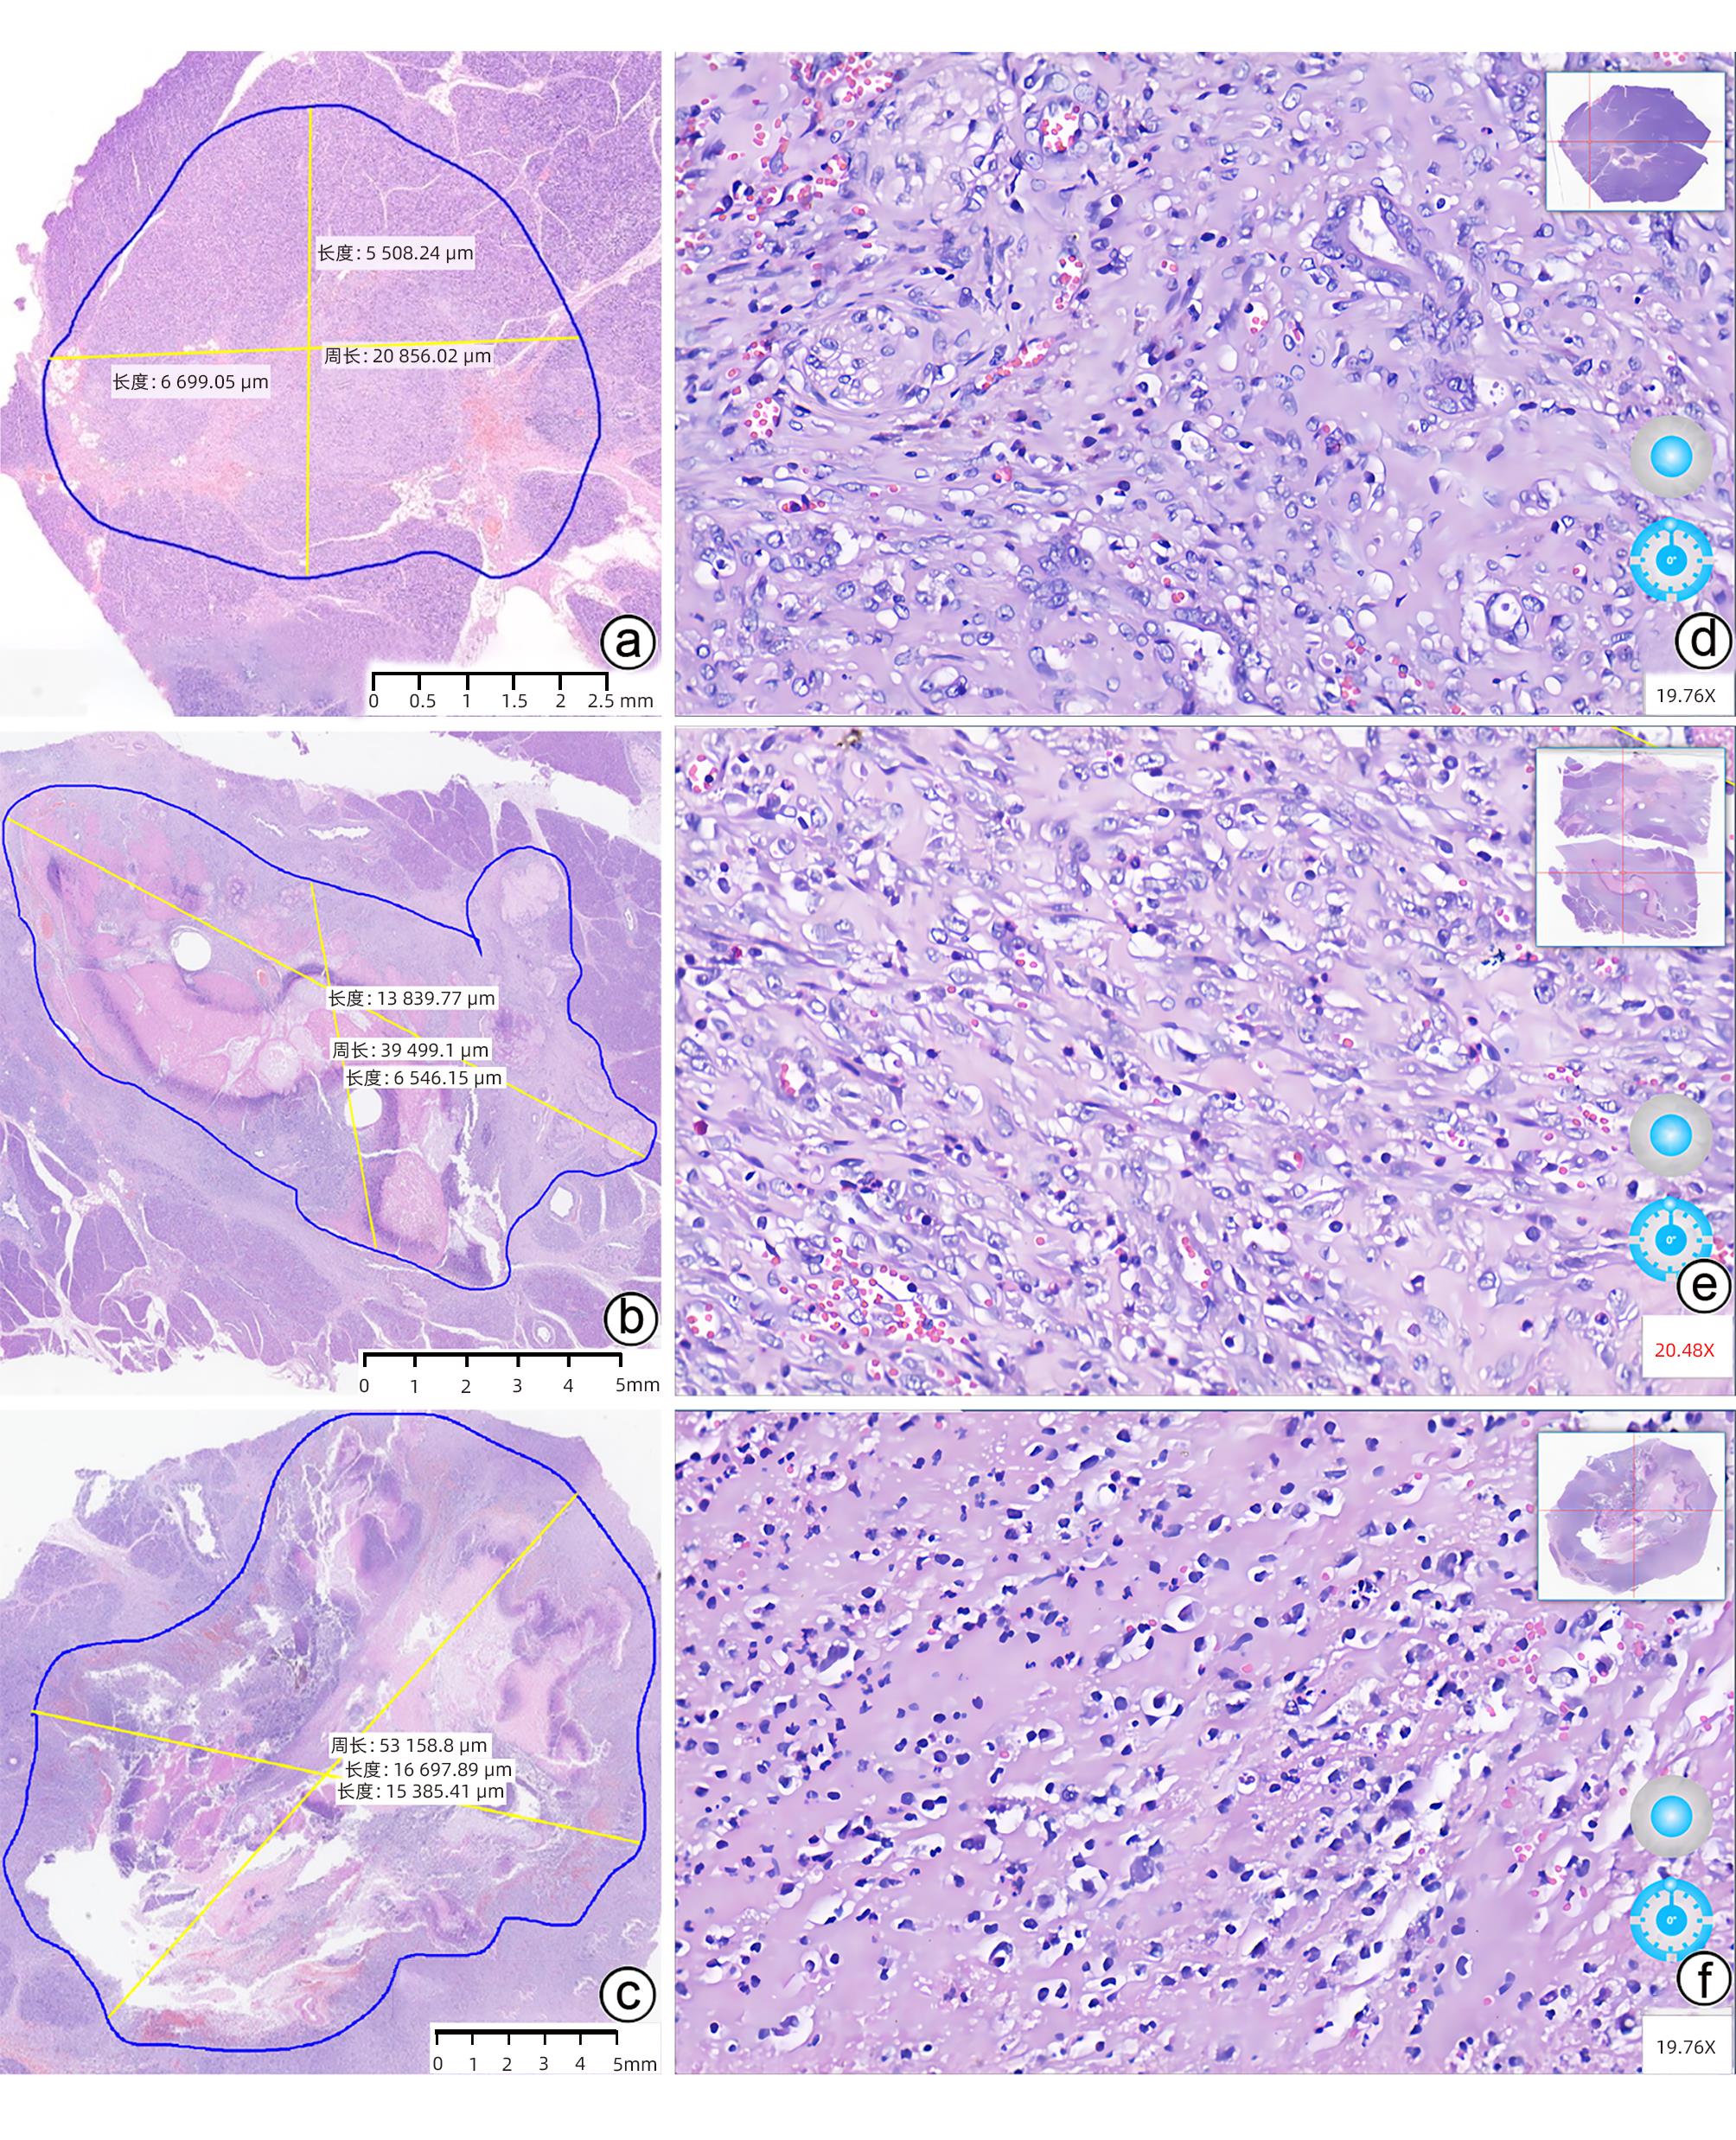

肝纤维化及肝硬化

乙型肝炎肝硬化异型增生结节患者中医体质类型分布及临床特点分析

方梦冰, 刘诚, 张玉, 曾嘉旖, 陈智恒, 黎胜, 池晓玲, 萧焕明

2024, 40(5): 961-967. DOI: 10.12449/JCH240515

摘要(1403) HTML (705) PDF (775KB)(71)

摘要:

目的  探讨乙型肝炎肝硬化异型增生结节(DN)患者中医体质分布特征,为肝癌癌前病变的防治提供依据。  方法  选取2015年5月—2023年3月在广东省中医院住院治疗的乙型肝炎肝硬化DN患者113例、乙型肝炎肝硬化再生结节(RN)患者105例、乙型肝炎肝硬化小肝癌(sHCC)患者70例。收集患者的年龄、性别、肝功能Child-Pugh分级、中医体质类型、实验室指标等资料。正态分布的计量资料多组间比较采用单因素方差分析及LSD-t法;非正态分布的计量资料多组间比较采用Kruskal-Wallis H检验;计数资料组间比较采用χ2检验,进一步两两比较采用Bonferroni校正法。  结果  乙型肝炎肝硬化DN患者以气虚质(27例,23.89%)、血瘀质(26例,23.01%)、痰湿质(23例,20.35%)为主。3组患者在痰湿质、湿热质占比方面比较差异有统计学意义(χ2值分别为6.822、6.383,P值均<0.05),从肝硬化RN患者、肝硬化DN患者到sHCC患者,痰湿质占比逐渐降低(30.48% vs 20.35% vs 14.29%),而湿热质占比逐渐升高(12.38% vs 16.81% vs 27.14%)。部分中医体质类型肝硬化DN患者在性别、Child-Pugh分级、前白蛋白、Alb、AST、TBil、总胆汁酸、甲胎蛋白上差异均有统计学意义(P值均<0.05),其中女性肝硬化DN患者气虚质占比高于男性患者(χ2=4.895,P=0.027);气虚质患者Child-Pugh A级占比低于Child-Pugh B级(χ2=6.380,P=0.012),而痰湿质患者Child-Pugh A级占比高于Child-Pugh B级(χ2=8.515,P=0.004);痰湿质患者前白蛋白、Alb水平高于其他4种体质患者(P值均<0.05),同时痰湿质患者TBil、总胆汁酸水平低于湿热质患者(P值均<0.05);阴虚质患者Alb水平低于气虚质、血瘀质、痰湿质患者(P值均<0.05);阴虚质患者甲胎蛋白异常比例显著高于非阴虚质患者(χ2=4.448,P=0.035)。  结论  乙型肝炎肝硬化DN患者以气虚质、血瘀质、痰湿质多见,痰湿质患者癌变可能性小,而湿热质、阴虚患者癌变风险较大。